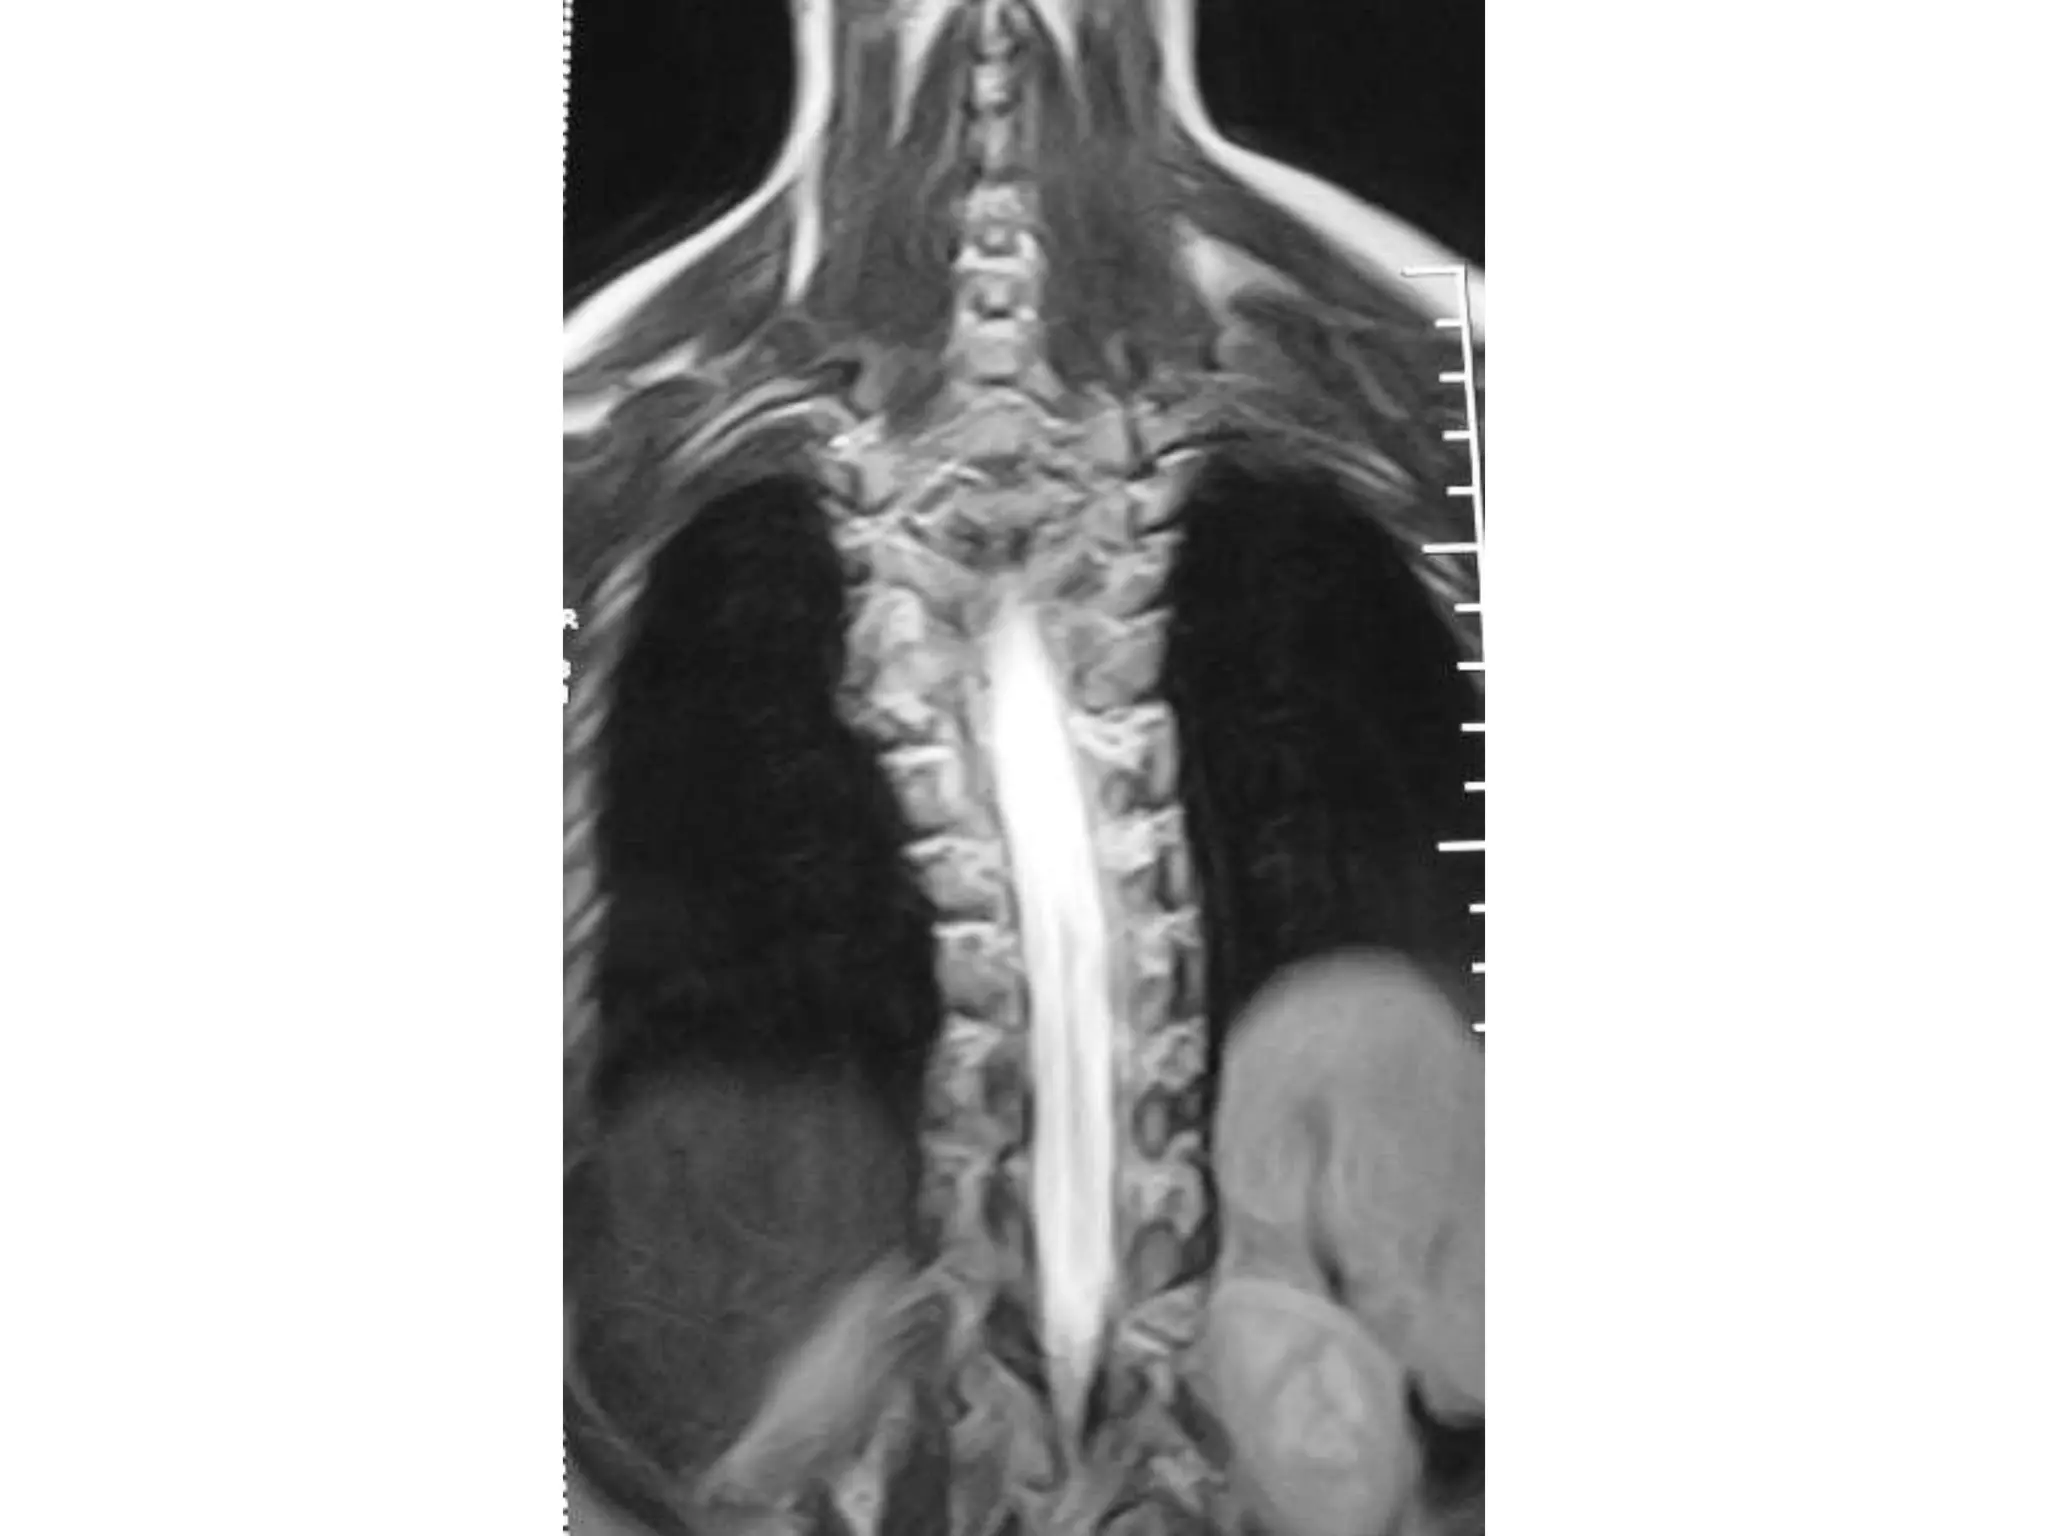

AV malformation